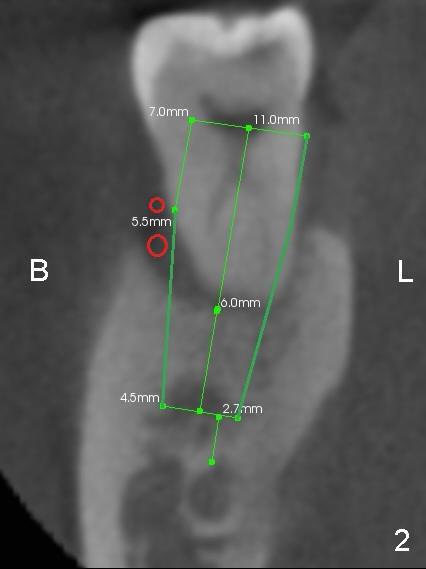

The tooth #31 of a 41-year-old man appears to have combined periodontitis and occlusal trauma: severe mesial bone resorption (Fig.1 (CT sagittal section),Fig.4 (PA)).  In fact, the tooth #32 was extracted when a 5x17 mm implant was placed at the site of #30 (Fig.4).

CT coronal sections at the mesial root of #31 show that a 7x17 (Fig.2) or 7x14 mm (Fig.3) implant does not look too large for the alveolar bone buccolingually.  The large implant is able to help close the large socket (mesial (Fig.1,4) and buccal (Fig.2,3) aspects), reducing the amount of bone graft (red circles) placed.  In contrast, the buccolingual width of #30 is narrower (Fig.9 CT coronal section), allowing a smaller implant (6x17 mm by design (Fig.9), 5x17 mm clinically (Fig.4)).